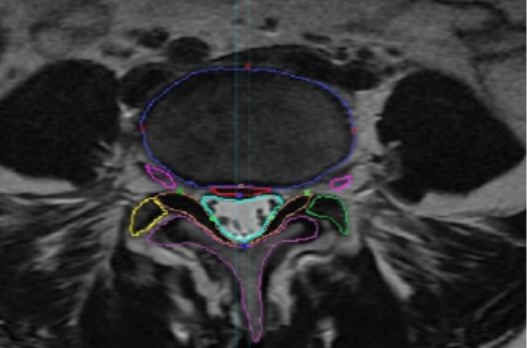

Automatic Segmentation of Lumbar Spine MRI Using Ensemble of 2D Algorithms

#1550

CoLumbo

Explore